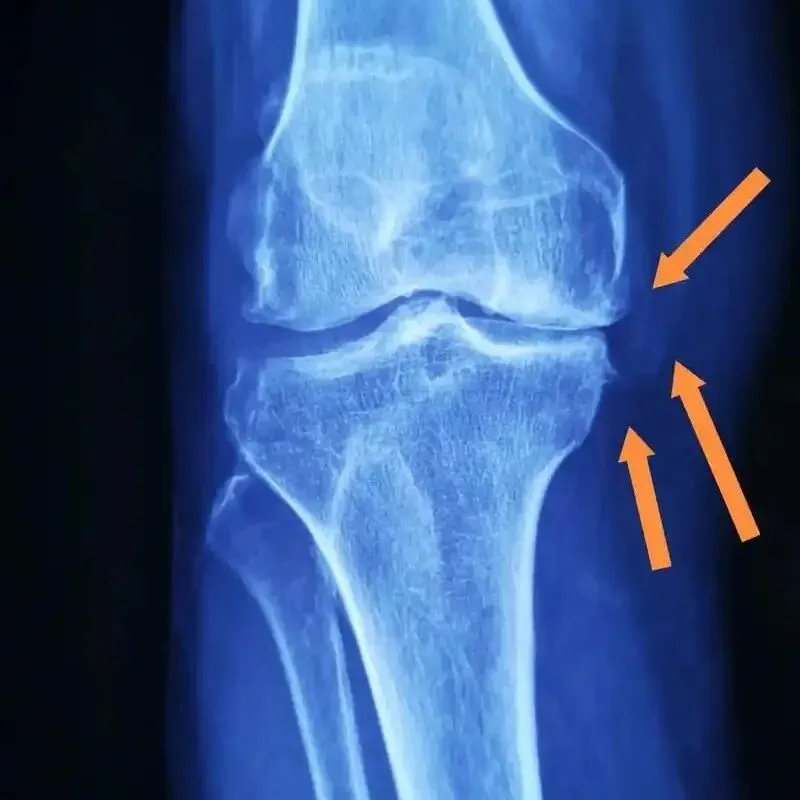

但类风湿患者的关节本身就存在损伤,过度劳累和负重会加重关节软骨磨损,诱发疼痛、肿胀。